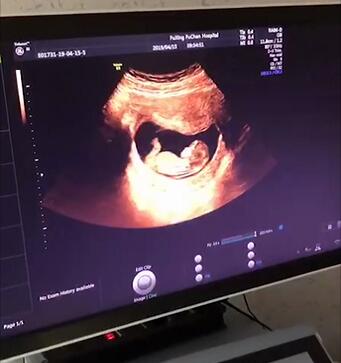

孕11-13+6周 NT检查

这个时期孕NT超声检查十分重要哦!

佛山都市妇产医院妇产科主任建议孕妈们在孕11-13+6周进行NT检查,

由专业超声医疗团队为您服务,提供准确的检查报告,

为孕妈们孕育健康宝宝提供了强有力的保障。